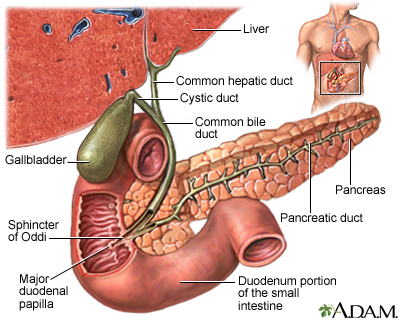

Choledocholithiasis means there is at least one gallstone in the common bile duct. The stone may be made up of bile pigments or calcium and cholesterol salts and are called common bile duct stones.

About 1 in 7 people with gallstones will develop stones in the common bile duct. This is the small tube that carries bile from the gallbladder to the intestine.